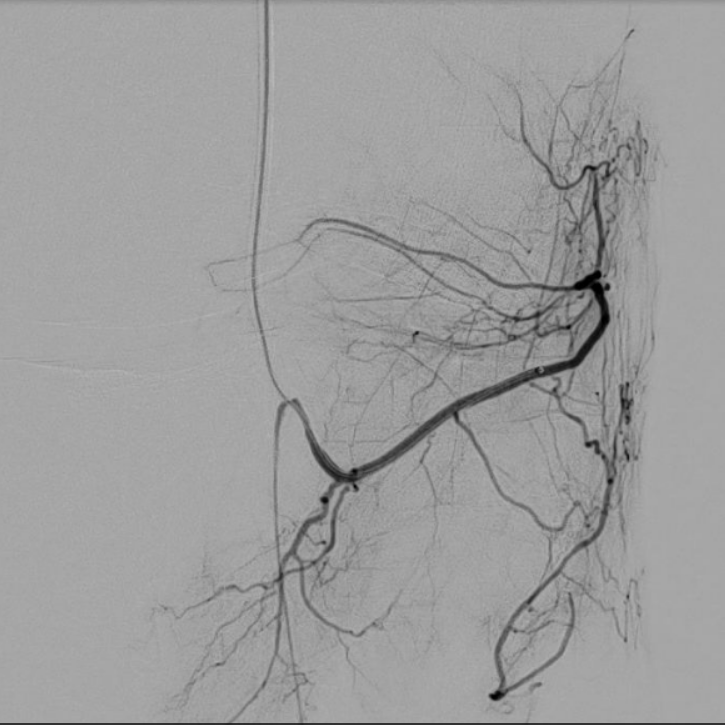

case of the day - 17.02.2026

Kniegelenk

Immer wieder eindrucksvoll, wie der ganze laterale Kniegelenksbereich über die A. genicularis inferior lateralis versorgt wird.

Arteria genicularis inferior lateralis - vor Behandlung

Arteria genicularis inferior lateralis - nach Behandlung